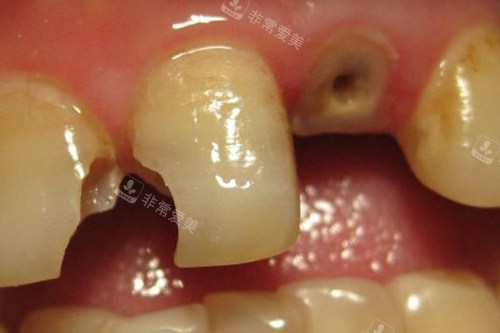

修复龋坏的牙齿

牙齿龋坏到牙根